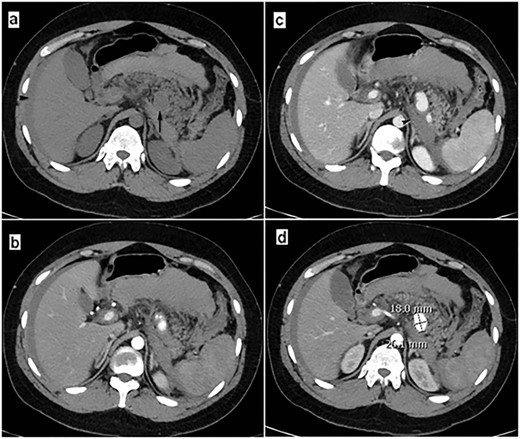

Twelve hours later, the patient complained of diffuse abdominal pain, while a decrease of hemoglobin was observed (9.5 mg/dL), and hemodynamic instability presented, with an increase in heart rate to 100 bpm. He was initially treated with intravenous fluids; surgical opinion was then seeked. Clinical examination revealed pronounced rebound tenderness on all of the abdominal quadrants and decreased abdominal sounds. In order to investigate the possibility of intraperitoneal bleeding and considering the stability of the patient, an emergency abdominal CT scan with i.v. contrast was indicated. CT scan revealed the presence of a ruptured proximal splenic artery aneurysm measuring 26 mm × 18 mm, 6 cm from its origin (Fig. 1).

Abdominal CT scan at the onset of patient’s hemodynamic instability: (a) CT-image before the iv contrast administration shows the aneurysm (arrow) and free fluid (blood) into the infraperitoneal space and peritoneal cavity (arrowhead). (b, c and d) Post contrast CT-images (arterial phase) reveal the ruptured aneurysm clearly the free blood collection into the infraperitoneal space (arrowhead).